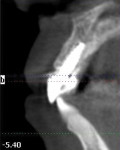

A 39-year-old nonsmoking male presented with a failing endodontically treated, fractured maxillary right central incisor. A draining sinus track was noticed at the mucogingival junction distal to the right central incisor (Figure 10). A pretreatment periapical radiograph demonstrated the large alveolar defect distal-apically (Figure 11). Clinically, the site registered a 12-mm probing depth at the distal line angle of the right central incisor. Following the technique previously outlined by the author, a preoperative administration of moxicillin and clavulanate potassium 875 mg 20 1 q 12 hours was started 1 day before the procedure. The patient was given the appropriate local anesthetic, the tooth removed, and the extraction site debrided by mechanical (curettage) and rotary instrumentation using high-speed handpiece with a round No. 6 diamond until all remnants of the periodontal ligament and granulation tissue were removed. A Tapered Screw Vent® implant (Zimmer Biomet Dental, zimmerbiometdental.com) measuring 4.7 mm x 13 mm was placed to the appropriate depth and achieved initial stabilization in the alveolar bone apical to the extraction site. An allogenic, mineralized cancellous, 1-mm to 2-mm-particle-size graft (Tutogen Medical GmbH, rtix.com) was placed into the remaining peri-implant defect, and condensed to completely fill the osseous defects and void in the preexisting buccal plate (Figure 12). A plastic provisional abutment was seated, and the preexisting full-coverage porcelain restoration was retrofitted to the plastic provisional abutment and served as the immediate provisional restoration. After a 3-month healing and maturation phase of the implant placed, the graft was inserted and the tissue was sculpted and held in place by the immediate provisional restoration, which allowed for a stable, mature soft-tissue emergence profile. The restorative clinician completed the final implant abutment and crown for the right central incisor. The patient followed regularly scheduled implant maintenance visits biannually. Figure 13 shows the 15-year post-treatment clinical view, and a 15-year post-treatment clinical view can be seen in Figure 14.